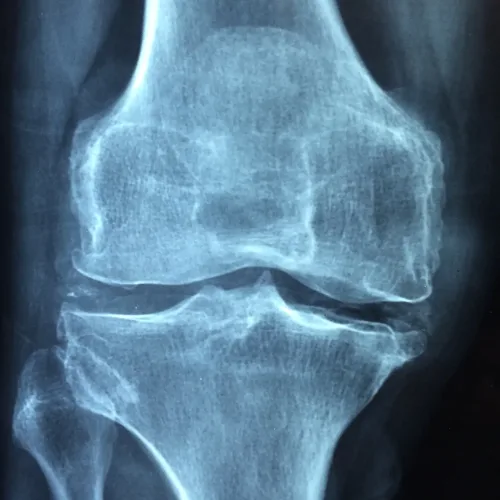

Osteoarthritis is a type of arthritis where the bone, cartilage and synovium wear down, leading to pain and stiffness. Synovium lines the joints and produces synovial fluid that lubricates the joins as well as supplies them with nutrients and oxygen. A 2016 study from the American Journal of Translational Research compared the effectiveness of acupuncture and physiotherapy for treating knee osteoarthritis. When looking at motor scores, pain, stiffness and physical function, those patients who received acupuncture had significantly improved scores compared to patients who received physiotherapy.

“This study revealed that both acupuncture and physiotherapy improved the clinical symptoms of pain, morning stiffness and joint dysfunction. However, acupuncture treatment showed better curative effect than physiotherapy, suggesting that acupuncture may be a superior non-operative treatment for KOA [knee osteoarthritis] compared with physiotherapy.”